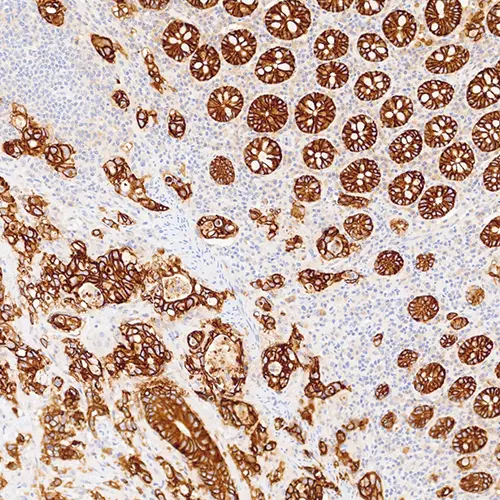

Bowel Adenocarcinoma: EpCAM clone EPR20532-222.

Epithelial Cell Adhesion Molecule (EpCAM) was one of the first tumor‐associated antigens identified and is a transmembrane glycoprotein expressed in most normal epithelial cells and overexpressed in a variety of carcinomas. It is involved in regulating normal cell-cell adhesion and may also have a role in the regulation of several oncogenes. It is not expressed in cancers of non‐epithelial origin, and therefore may be used as an aid for the differential diagnosis of several conditions.

EpCAM is recommended for the detection of specific antigens of interest in normal and neoplastic tissues, as an adjunct to conventional histopathology using non‐immunologic histochemical stains.